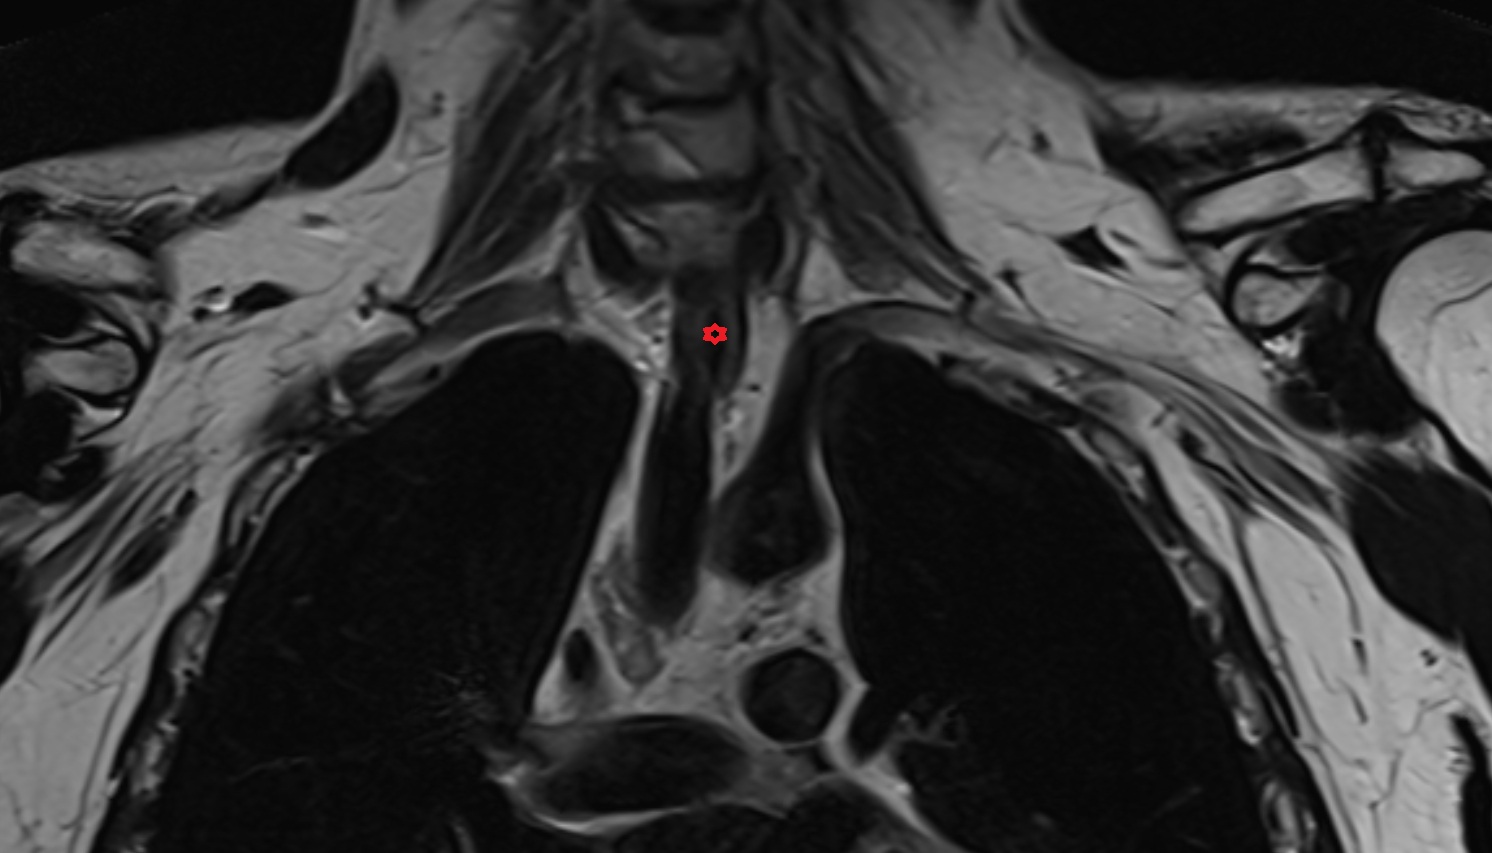

- Spinal cord

- Upper cervical spinal cord

- subarachnoid space of spinal cord